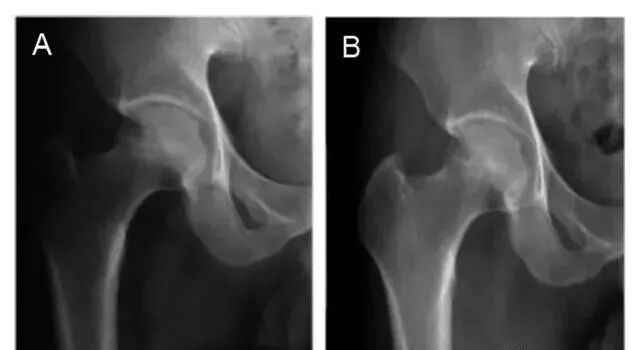

图中A和C:典型病例术前正位和蛙式位X射线片,股骨头内不规则高密度影;

图B和D:典型病例术后7.5年正位和蛙式位X射线片,股骨头外形规整,无塌陷。